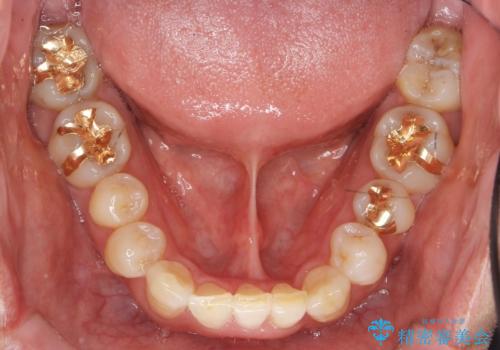

奥に引っ込んでいる歯をセラミックでかぶせたい 補綴前矯正 50代男性

- 神経が死んでいる前歯2本(右上21)をセラミッククラウンでかぶせたいとご希望され、来院された患者様です。

歯並びにより、そのままだときれいに被せ物をいれられない状態でした。

補綴前矯正としてマウスピース矯正(インビザライン)を行った後、セラミッククラウンによる補綴治療を行いました。

重度の叢生(歯並びのがたがた)のため、

患者様の「できるだけ短期間で治療を終わらせたい、セラミックが入れられたら良いので大がかりなことはしたくない」とのご要望により、3Dシミュレーションを何度も行い患者様とのコンサルを重ね、上顎左右犬歯と左下2を抜歯して②のプランである補綴前矯正(インビザライン)を行うことにしました。